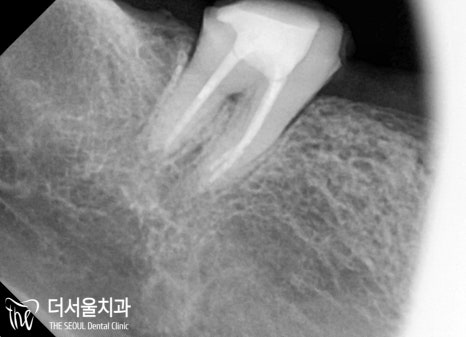

파노라마로 좀 더 자세히 살펴볼까요?

주변 치조골이 다른 곳에 비해

약간씩 오목하게 들어가 있는 것을 확인할 수 있죠.

염증이 진행되어 잇몸, 그리고 잇몸뼈까지

악화시킨 것으로 판단이 됩니다.